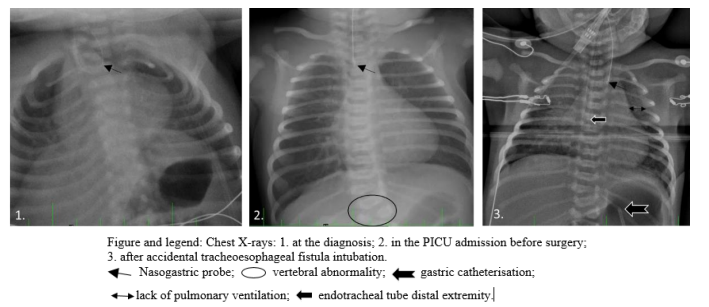

A three-day-old female had emergency surgery for type C esophageal atresia (EA) planned by thoracoscopy. The child was born full-term, 3480 g. The antenatal diagnosis of EA went unnoticed despite moderate polyhydramnios observed during the latest ultrasound. After birth, she had worsening feeding difficulties associated with hypersalivation respiratory distress with cyanosis, and significant bronchial congestion. The neonate received nasal oxygen and EA was diagnosed after a chest x-ray, showing a gastric tube coiled in the esophagus and gastric aeration (figure). Vertebral abnormalities were found, and a blood test and cardiac ultrasound were normal. Before anesthesia induction, the child’s weight was 2990 g, hemodynamic parameters were normal and Sp02 95% under 1 L/min nasal oxygen without CPAP. The preoperative flexible tracheoscopy in spontaneous ventilation under sevoflurane showed a large distal TEF near the carina. After an IV injection of 0.8μg sufentanil, 20 mg ketamine and 5 mg propofol, a 3.0 mm endotracheal cuffed tube (ETT) was easily inserted. We inserted the ETT to try to place its distal extremity beyond the fistula orifice. Immediately, we observed essential difficulties in mechanical ventilation leading to hypoxia (Sp02 55%) and bradycardia (60-80 bpm) with abdominal distension. We did not notice any capnogram and pulmonary auscultation was not helpful. External cardiac massage was started immediately, and the patient received 3 bolus of 50 µg adrenaline and a vascular filling of 2 g of albumin. The surgeon did a percutaneous gastric puncture with an IV cannula to deflate the gastric distension. The ETT position was checked again by laryngoscopy. We found no abnormal path of the tracheal tube or pneumothorax on the chest radioscopy done in the operating room. A tracheal suction probe did not retrieve any secretions in the ETT, but the probe was caught at its end. Therefore, the diagnosis was the accidental intubation of the esophageal fistula by the tracheal tube. We decided to remove the tube and performed another tracheal intubation. We immediately noticed an improvement in all the respiratory and hemodynamic parameters. Pulmonary auscultation was symmetrical. The entire episode lasted for few minutes, during which the resuscitation manoeuvres made it possible to maintain acceptable oxygenation and hemodynamic parameters. The surgery, initially planned by thoracoscopy, was performed by thoracotomy. The procedure was carried out without particular difficulties, and the infant was consequently transferred to the PICU. The mechanical ventilation was stopped on day 5; enteral alimentation was started by transanastomotic gastric tube on day 6. The girl was discharged from the hospital on day 26 with a good evolution without any neurologic sequelae. The 3-month follow-up was satisfactory regarding the digestive, pulmonary, and neurological aspects.

During EA surgery, accidental intubation of the tracheoesophageal fistula (TEF) has been sparsely described [4,6-9], leading in some cases to the death of the patient [7,8]. The diagnosis of EA with TEF is often delayed until after birth, with symptoms such as feeding difficulties, hypersalivation, as well as aspiration pneumonia [1,3]. EA diagnosis is confirmed when a blockage of the gastric tube in the end of the esophagus is visible on a chest X-ray (figure). The importance of identifying a TEF is currently well demonstrated in the literature [1-3,7,8,10,11]. The gold standard is a pre-operative bronchoscopy to determine the TEF characteristics (size, position, number), and to research potential tracheal abnormalities [2,3,7,10,12]. Recent studies have shown that only about half of EA cases benefit from a preoperative bronchoscopy [2,5,7]. A bronchoscopy study of 113 newborns with EA, by Holzki and al, described 67% of TEF cases above the carina, 22% within 1 cm of the carina and 11% at the carina or below it [12]. In this case, despite our experience, we initially did not consider the possibility of this adverse event leading to a delayed diagnosis of TEF intubation. We first eliminated esophageal intubation, bronchospasm, hypovolemia, pneumothorax, obstructive secretions in ETT, before considering this event. We couldn’t check the ETT placement with the bronchoscope because it was too wide, and direct laryngoscopy [8,11] and chest X-ray were not helpful (figure). Our pediatric hospital has no fiberscope thin enough to pass through a 3 mm ETT. The child’s weight might have allowed us to insert a 3.5 mm ETT, enabling us to perform a bronchoscopic control.

Various techniques have been described in the literature to prevent ventilation problems associated with TEF. The historical technique is to place distal extremity of the ETT below the orifice of the TEF: it must be placed up to the carina and then withdrawn, until obtention of symmetrical pulmonary auscultation [2-4,11]. The anesthetist can also rotate the ETT to close the TEF orifice with the bevel of the tube [2,11]. Another possibility described is to perform selective intubation in the left main bronchus until ligation of the TEF [11,13]. Still, there is always a potential risk of increasing ventilation difficulties and gas exchange disorders. Other teams have suggested using a Fogarty balloon catheter, or endobronchial blocker, to close the TEF [2-4,10,11,14]. This technique is uncommon due to implementation difficulties alongside or through the ETT and the risk of secondary displacement [3,11]. A recent article suggests performing a real-time ultrasound air visualization in the stomach to optimize the ETT placement [15]. In our case, the chest X-ray review could have suggested TEF intubation due to the absence of lung parenchyma ventilation and persistent gastric distension (Figure). The ventilation management of EA has been discussed for many years but there is still no firm consensus. This confirms the real difficulties encountered by medical teams involved in EA. The means of solving them depend on the experience of the various stakeholders (anesthetists, surgeons, otolaryngologists, neonatologists, gynecologists) and the use of all technical resources available. Due to EA’s rarity, the individual experience of each practitioner is minimal. This lack of experience leads to difficulties in setting up consensual protocols. These concerns were recently addressed by the European Reference Network on Rare Inherited and Congenital Anomalies (ERN-ICA), which published in 2020 the first international guidelines [16]. They advocate the need to manage at least 5 EA per year by specialized team, in order to develop optimal support [1]. But these recommendations rely on the uncontrollable random number of EA births. An investigation in 2012, showed that 67% of surgeons operate on 1 to 3 EA each year [2]. On the other hand, there is evidence that even skilled anesthetists may have difficulty intubating EA while excluding TEF [11,15].